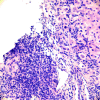

BACKGROUND Systemic lupus erythematosus (SLE) is a multiorgan immunologic disease which commonly results in systemic manifestations by involving joints, kidneys, skin, heart, hematologic cell lines, pulmonary and central nervous systems. The hepatic involvement of lupus is relatively less common, which creates diagnostic challenges, as the clinical presentations of lupus hepatitis and autoimmune hepatitis (AIH) are similar. CASE REPORT A 51-year-old woman presented for multiple joint pain that began 2 years ago. Her work-up, including kidney biopsy, was consistent with a diagnosis of class V lupus nephritis. Subsequently, within a few months, she was admitted with acute elevation of liver enzymes and high immunoglobulin IgG level, and a liver biopsy demonstrated impressive interface hepatitis with many plasma cells and lymphocytes, suggestive of chronic hepatitis with high histological activity. This case illustrates the co-presentation of lupus nephritis and AIH, which is a rare association. The patient was managed with a tapering dose of prednisone, hydroxychloroquine initially, and later with mycophenolate mofetil, with complete resolution of liver enzyme abnormalities by 4-month follow-up. CONCLUSIONS Lupus hepatitis is hepatic involvement of SLE, which should be distinguished from AIH. Accurate diagnosis is important, as management and prognosis of these immunologic conditions can differ. Although both entities share clinical and biochemical markers, the presence of anti-ribosomal P antibodies and liver histology features of predominant lymphoid infiltrates with lobular inflammation favor lupus hepatitis. A multidisciplinary approach involving rheumatologists, hepatologists, and pathologists can improve disease outcomes by properly differentiating the 2 entities and guiding the selection of appropriate immunosuppressive therapy.